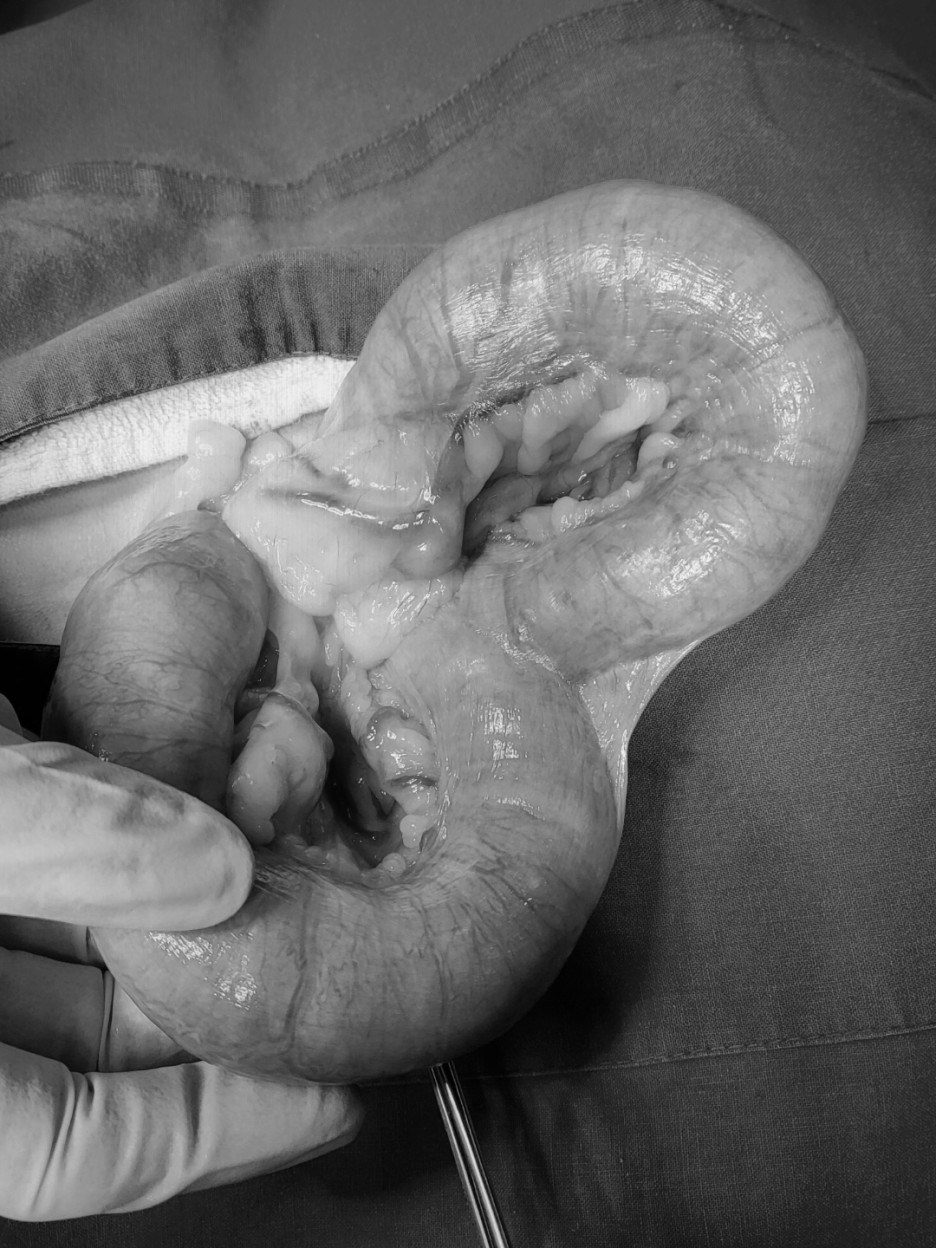

실제로 강아지의 자궁낙농증 치료를 위해 저희 병원을 내원한 많은 어린이들이 이런 경우가 많으며 수술 후 사진을 보면 자궁이 원래보다 수십 배 확장되고 있습니다.

제거한 자궁과 난소

자궁체 절제 → 제거한 자궁 → 자궁내 혈액성 농성 삼출물

강아지의 자궁축농증이 있는 자궁은 이렇게 쌓인 고름처럼 사진처럼 팽창하게 된다.

이 환자의 자궁 내에는 혈액성 농성 삼출물로 가득 차 있었습니다.